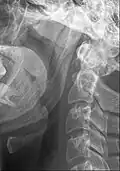

Ossified stylohyoid ligament or elongated styloid process Ossified stylohyoid ligament or elongated styloid process